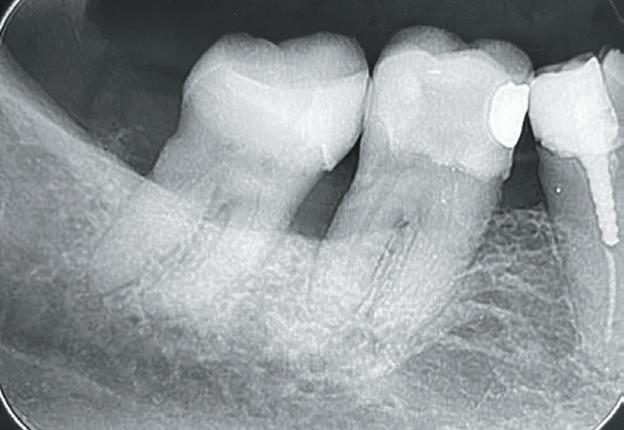

Un pacient caucazian în vârstă de 77 ani s-a prezentat la clinica autorului după cinci ani în care nu a fost la niciun control stomatologic. Examinarea clinică a arătat o pierdere semnificativă de os, parodontită cronică și multiple edentații care au destabilizat ocluzia. Pacientul a raportat sensibilitate la rece la nivelul primului molar drept inferior nr. 46, în special la ingerarea de lichide reci. Radiografia periapicală a confirmat constatările examenului clinic; în

plus, s-a detectat și prezența unei carii radiculare la nivelul rădăcinii distale a aceluiași molar, cu răspuns pozitiv la testul de sensibilitate (fig. 1-2).

1. Situația clinică inițială.

2. Radiografia inițială.